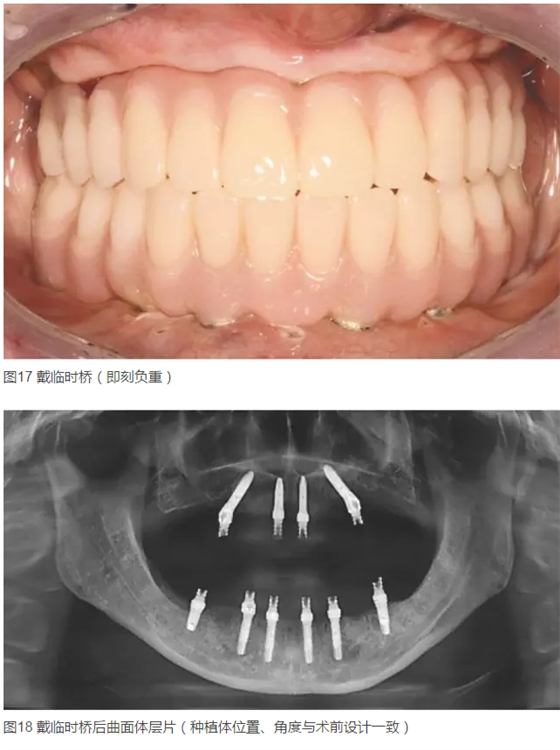

患者女,42歲。1年前因牙周病拔除全口牙齒,行全口活動(dòng)義齒修復(fù),現(xiàn)自覺影響咀嚼和生活來診。要求:牙種植修復(fù)后即刻可使用。